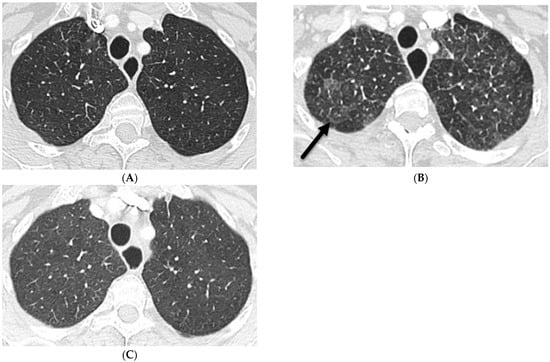

4.3. Immunotherapy-Related Side Effects

4.4. Electronic Cigarette or Vaping Use-Associated Lung Injury (EVALI)

| Electronic cigarette or vaping product use-associated lung injury (EVALI) | smooth | + | + | + | − | − | − | − | + | +/− |